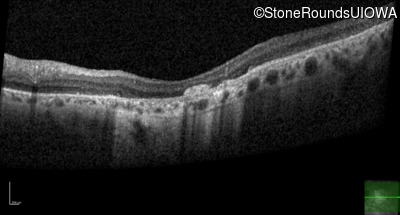

Optical Coherence Tomography - Left - 20/80

Exemplar / OCT Stack

Infrared Fundus Photograph - Right - 20/125 -2